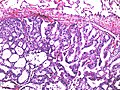

Lung metastasis (Ewing sarcoma). H&E stain. | |

Microscopic

Features:

- Variable - dependent on site of origin.

- Colorectal adenocarcinoma - usually distinctive morphologically:

- Typically gland forming.

- Ellipsoid/elongated pseudostratified nuclei with moderate nuclear atypia.

- +/-Dirty necrosis.

Lung metastasis (ES) - intermed. mag. (WC/Nephron)